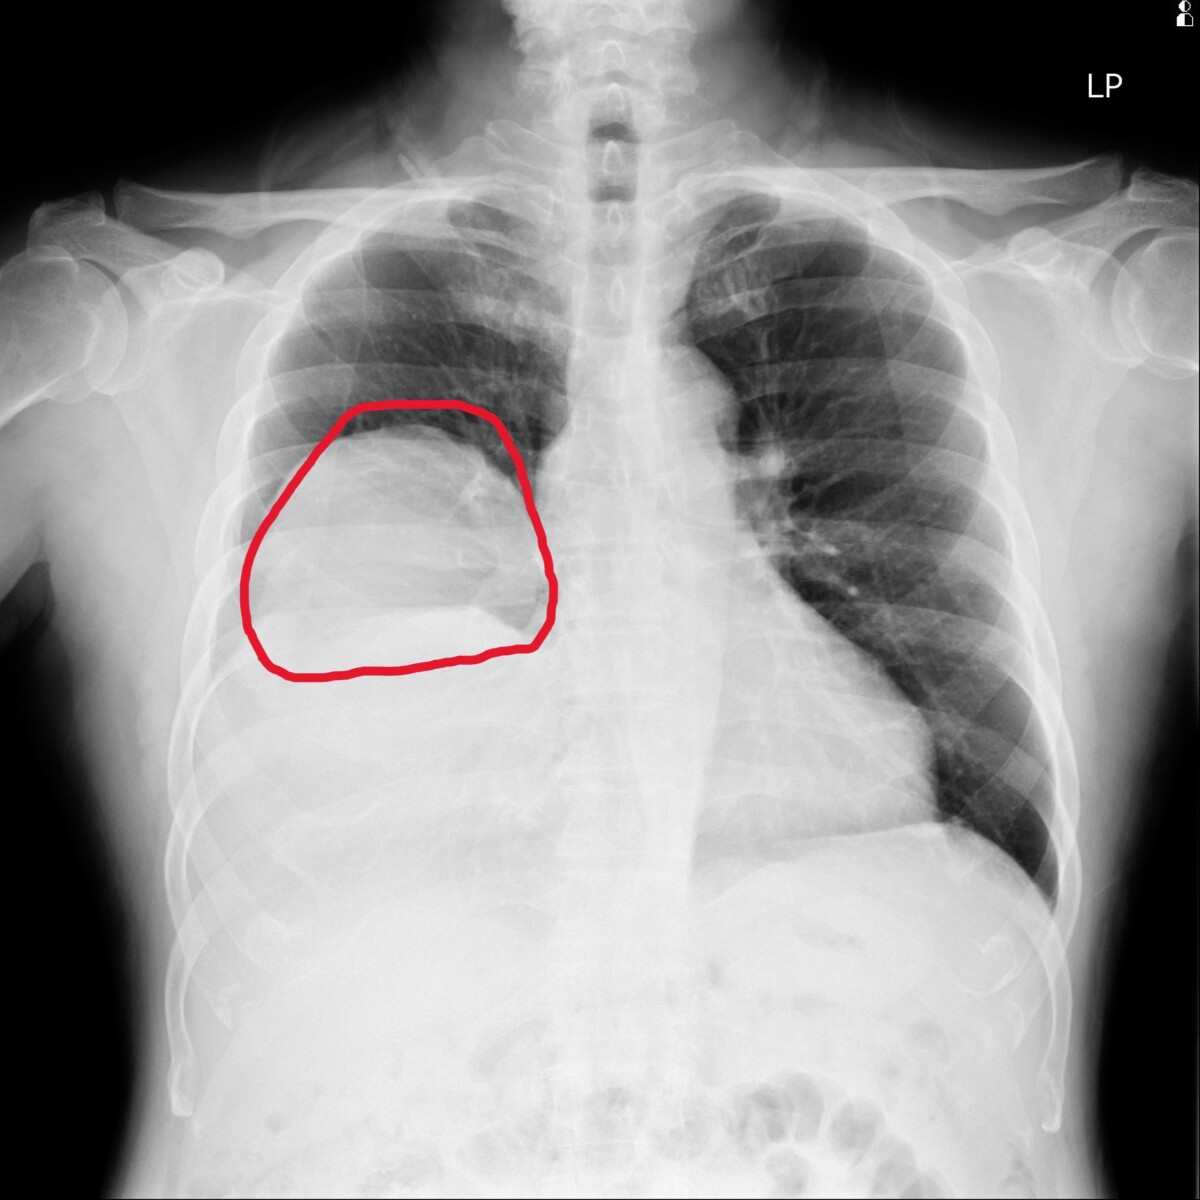

▲70歲男反覆低血糖昏迷,檢查驚見右肺15公分腫瘤,確診罕見腫瘤相關低血糖症,術後恢復良好。(員榮醫院提供)

▲70歲男反覆低血糖昏迷,檢查驚見右肺15公分腫瘤,確診罕見腫瘤相關低血糖症,術後恢復良好。(員榮醫院提供)

患者先至員榮醫院新陳代謝科就診,由塗宜育評估後發現,其糖化血色素正常(5.4%),但空腹血糖偏低,初步排除常見糖尿病或藥物因素,懷疑為非典型低血糖,遂安排住院進行72小時禁食測試與完整影像檢查。

住院期間,患者仍頻繁發生低血糖,血糖多次低於30 mg/dL,需持續注射高濃度葡萄糖維持生命穩定。進一步胸部影像檢查發現,右肺存在一顆約15×11公分巨大腫瘤,並伴隨肋膜積液與淋巴結腫大。

院方隨即會診胸腔專科,由涂川洲參與評估,醫療團隊高度懷疑為罕見「腫瘤相關低血糖」,可能與腫瘤分泌類胰島素生長因子(IGF-2)有關,屬於非胰島素瘤性低血糖症(NICTH)。